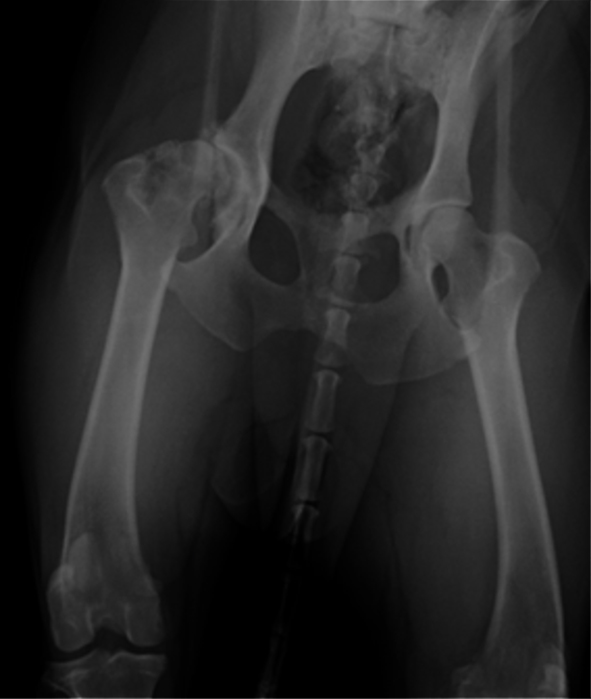

②股関節形成不全により慢性的な変形性関節症に罹患している10歳のラブラドールレトリバーのX-ray写真です